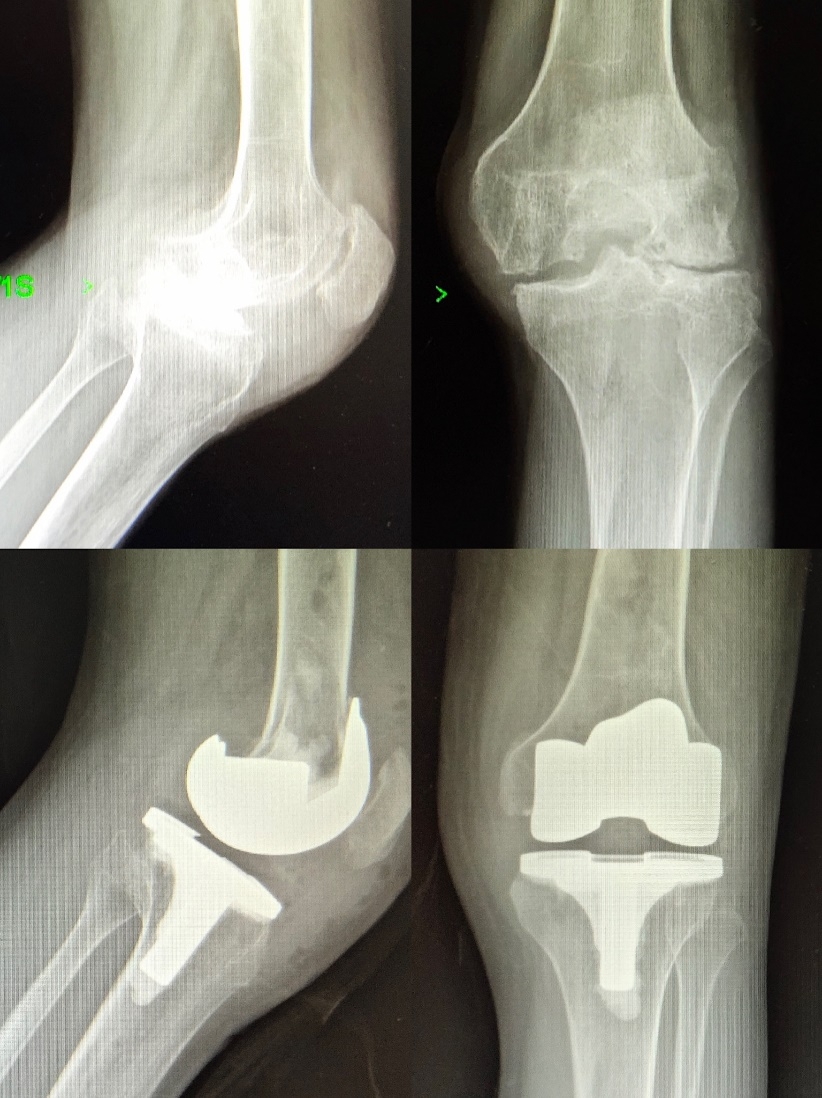

2019年8月13日和9月12日,由科室主任史占军教授主刀,为3位饱受膝关节炎病痛折磨的患者实施了全膝关节置换手术,术中首次使用了安择™膝关节,再次证明了施乐辉国产膝关节与一直以来提供的进口假体有着同样的品质。

史占军教授手术后对此款假体感受颇深,最大的改进在于前髁收窄设计,能够避免前髁的悬挂以及对周围软组织的刺激,它在假体和工具的设计上都给我们提供很好的帮助,这是南方医科大学南方医院的首款国产膝关节假体,相信它将是一个新的里程碑。

患者术前术后光片